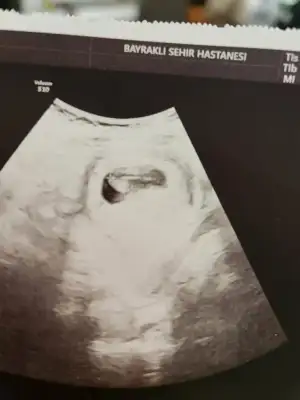

Kese oluşuyor bebek oluşmuyor muşBir de sizin rahimde kese görünmedi mi kese göründükleri sonra dış gebelik şüphesi kalmaz ki

Yemin ederim bak durum aynı şöyle kız direk alttan muayene etti bi bebek var dedi bi yok dedi ama kalp atışı var dedi sonra aleti çevirdi bebek çok küçük şurada dedi sonra ultrason cihazı kaliteli değil net görüntü vermiyor dedi ama için rahat olsun kalp atışı var bebek küçük dediUltrason kalitesine bağlı oluyor genelde canim mesela oğlumda 2 kere kese gördüm gittiğimde sonradan gittiğimde bebek vardı kızımda 6 haftalikken kalp atışını bile duymustum

Rahat olsun canim icin o zmn dediğim gibi cihazdan kaynaklıdır kalp atışını görmüş sonuçta görmese bile söylemek zorunda en kötüyü bile söylüyorlar şükür senin bebegin senleYemin ederim bak durum aynı şöyle kız direk alttan muayene etti bi bebek var dedi bi yok dedi ama kalp atışı var dedi sonra aleti çevirdi bebek çok küçük şurada dedi sonra ultrason cihazı kaliteli değil net görüntü vermiyor dedi ama için rahat olsun kalp atışı var bebek küçük dedi

Ne güzel işte kalp atışını görmüş çok küçük demek ki ve ultrason cihazı çok fark ediyor ama önemli olan doktorun kalp atışını görmesi sesi sonradan dinlenirYemin ederim bak durum aynı şöyle kız direk alttan muayene etti bi bebek var dedi bi yok dedi ama kalp atışı var dedi sonra aleti çevirdi bebek çok küçük şurada dedi sonra ultrason cihazı kaliteli değil net görüntü vermiyor dedi ama için rahat olsun kalp atışı var bebek küçük dedi

Rabb'im kimseye yaşatmasın canım ben gittim acile ultrason cihazı kötü dedi ama kalp atışı var bebek çok küçük daha için rahat olsun dediO boş gebelik geliyor dış gebelikte gebelik kesesi rahim dışına yerleşir ve çok kötü bir durum